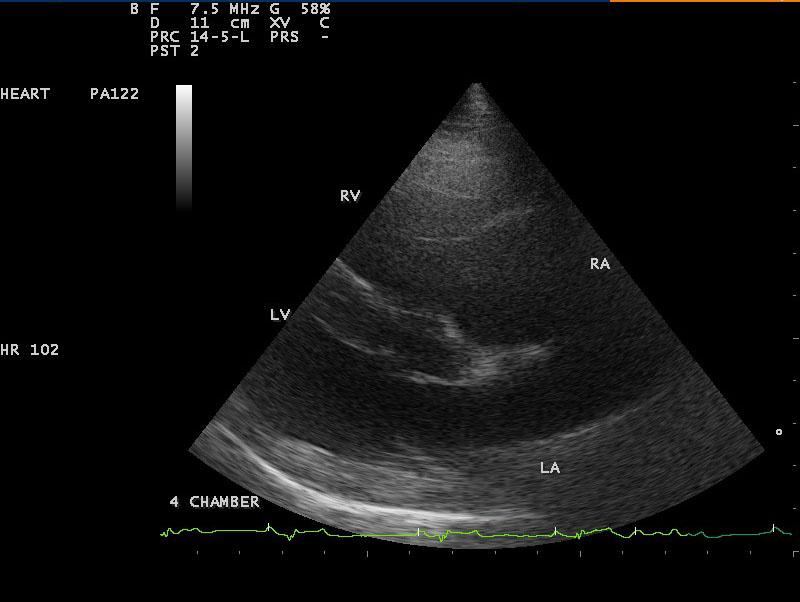

A 10-year-old SF Labrador was presented for evaluation of ascites, which was quantified as a modified transudate. Additional history on this dog was that 11 months prior an ovariohysterectomy and resection of mammary gland tumors had been done. The tumors were benign on histopathology. On abdominal ultrasound, the ascites, hepatic congestion, and a dilated CVC were present.